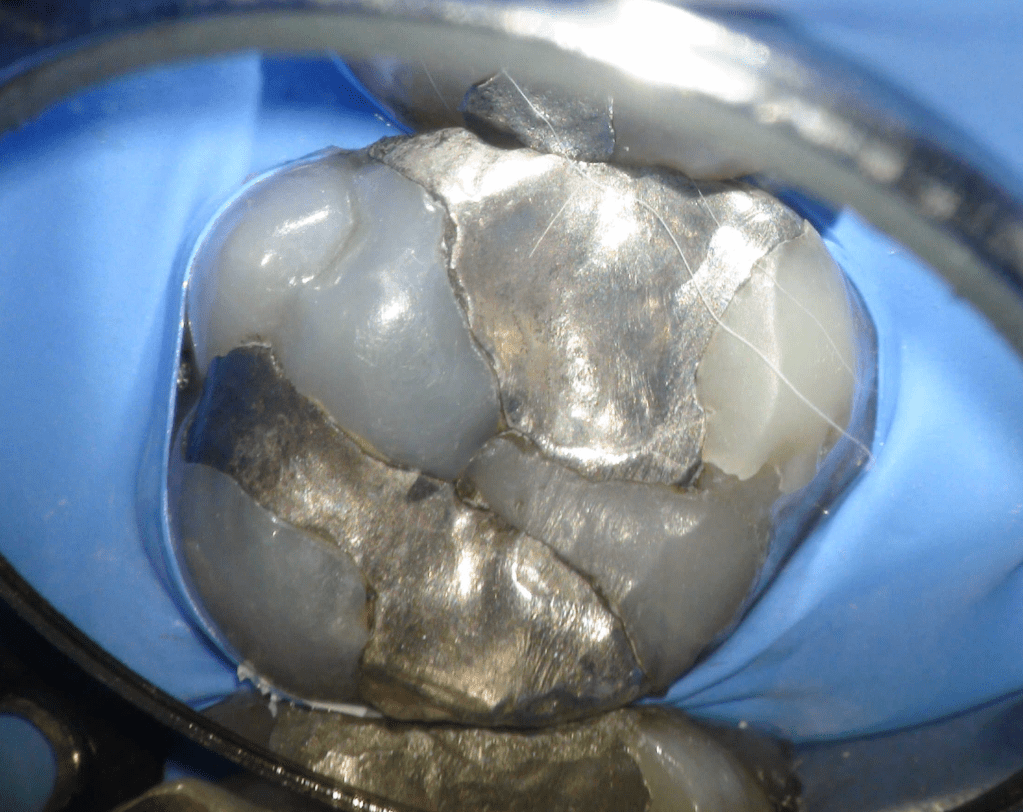

Fisura, remoción amalgama para explorar